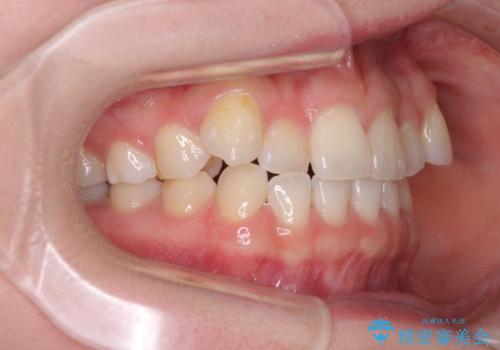

口腔内の状況を確認したところ、左右ともに下顎第二大臼歯が欠損しており、咬み合うべき上顎の第二大臼歯が著しく挺出していました。

挺出した大臼歯を元の位置に戻すことは現実的に難しいため抜歯することとし、補助装置とワイヤー装置により上顎歯列全体を後方に移動することとしました。